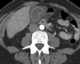

Diffuse gallbladder wall thickening

Cholecystitis is inflammation of the gallbladder. Symptoms include right upper abdominal pain, nausea, vomiting, and occasionally fever. [Source: Wikipedia ]